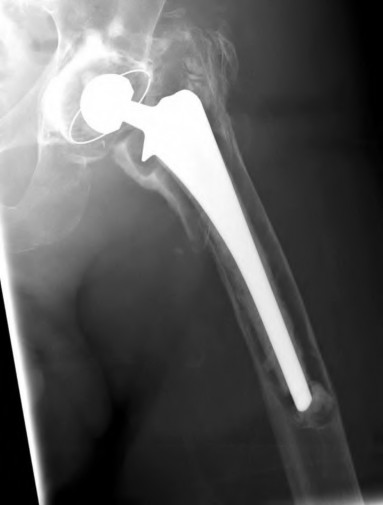

A 72-year-old male presents 2 years status post fixation of an impending pathologic right femur fracture due to metastatic renal cell carcinoma. He is minimally ambulatory due to pain. Despite radiation therapy, there has been progression of the lesion with extensive cortical bone loss, which is shown in Figure A. A proximal femoral replacement arthroplasty is performed without complications, and is demonstrated in Figure B. Which of the following is true regarding this patients post-operative course?

Deep prosthetic infection is the most common complication after hip arthroplasty performed for salvage of failed internal fixation after pathologic proximal femoral fracture secondary to malignancy.

Jacofsky et al reviewed the complications in 42 patients with a mean age of 63 who were treated with hip arthroplasty for salvage of failed treatment of a pathologic proximal femoral fracture. Multiple different constructs were used.

The most common complication was deep prosthetic infection, which occurred in nearly 10% of the patients studied. All infections occured in patients whom had previously received radiation. The mean Harris Hip score improved from 42 to 83 points post-operatively, and 41 of the 42 patients were ambulatory at follow-up. Implant survivorship free of revision for any reason at 5 years was 90%, and free of revision for aseptic failure or radiographic failure was 97%.

Figure A shows a lytic lesion of the proximal femur with an intramedullary implant. Figure B shows a proximal femoral replacement.